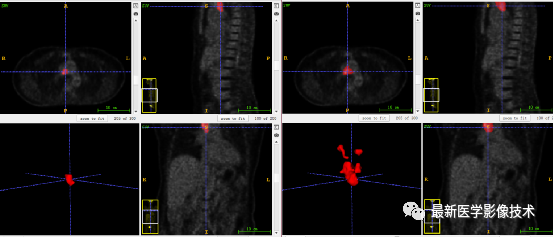

7、验证集分割结果:输入整个图像通过滑窗叠加预测结果,左图是金标准,右图是预测结果